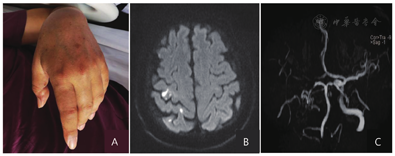

患者男性,59岁,因"左手活动不利12 h"于2022年4月2日入院。患者自述当日12 h前无明显诱因出现左手活动不灵,表现为左手不能抓握和伸展,伴有腕下垂(图2A),不伴感觉麻木,左上肢抬举正常,下肢行走正常,无言语不利,无饮水呛咳、吞咽困难,无头晕、视物旋转、视物双影,无耳鸣、耳聋、听力下降,无头痛、恶心、呕吐,无胸闷、胸痛、心悸,无腹痛、腹泻。急诊颅脑CT平扫大致正常,以脑梗死收入秦皇岛市第一医院神经内科治疗。既往有高血压史10年,最高血压192/93 mmHg,平素口服硝苯地平控释片(30 mg,1次/d),血压控制在160/90 mmHg左右;有糖尿病史5年,平素注射门冬胰岛素(早26 U、晚24U),血糖控制不佳(具体不详);左下肢动脉支架置入术后2年。

左手表现为"腕下垂"(A);颅脑弥散加权成像示右侧中央前回手结节区和中央后回病变(B);颅脑磁共振血管成像示右侧颈内动脉、大脑中动脉和大脑后动脉显影不良(C)

入院后给予双重抗血小板、稳定斑块、改善循环和清除自由基等治疗。辅助检查:血红蛋白111 g/L,平均血红蛋白体积76.8 fl,铁蛋白15.55 μg/L,糖化血红蛋白7.9%;肝肾功能、血脂、心肌酶未见异常;凝血功能、风湿三项(C反应蛋白、类风湿因子、抗O抗体)、肿瘤标志物、甲状腺功能未见明显异常。胸部CT、心电图、心脏彩超大致正常。颈部血管彩超示右侧颈内动脉起始部管腔中度狭窄。MRI提示右侧点片状新发散在梗死灶(图2B),磁共振血管成像示右侧颈内动脉未见显影,右侧大脑中动脉近端狭窄,远端未见显影,右侧大脑后动脉狭窄(图2C)。双上肢肌电图未见明显异常。

2022年4月4日,患者左手拇指和食指可轻度活动,但腕部不能活动。查体:左手拇指内收和食指屈肌肌力2级,左手其他手指肌力0级,左腕部屈伸肌肌力0级。4月11日出院时,左手拇指内收和食指屈肌肌力3级,中指、环指、小指屈肌肌力2级,腕部屈肌肌力2级,余手指肌力0级,腕部伸肌肌力0级,美国国立卫生研究院卒中量表评分0分,mRS评分2分。出院后继续手部康复、双重抗血小板、稳定斑块、控制血压和口服丁苯酞软胶囊(2粒,3次/d)3个月。2022年5月28日随访时左手屈伸好转,查体见左手屈伸肌肌力4级,余肌力5级,mRS评分1分。

手结节区受累的常见临床症状表现为桡侧手麻痹、尺侧手麻痹或完全手麻痹,伴或不伴有腕下垂及感觉障碍[12],但有时也可单纯表现为食指麻痹[13]。关于全手均匀麻痹类型,文献报道的受累病变结构多为条形梗死,累及倒置"Ω"区整个桡臂侧或局限于其上方或结节区广泛受累[14]。病例1表现为"爪形手",在发病初期左手指不能完成屈伸、内收和外展动作,颅脑MRI可见病灶范围较大,累及整个手结节区(图1B和C);病例2累及整个桡臂侧及上方并伴有腕下垂(图2A和B)。此外,病变累及中央沟底部以及中央前回后缘也有报道[15]。除手结节区受累外,功能MRI发现中央后回受累也可引起手部运动障碍[3]。对这种现象的解释,首先是中央后回出现中央前回特有的锥体细胞,其次是中央后回有助于锥体束形成,并可被运动任务的传出部分激活。此外,当手及手指执行运动任务(位置变化)时,需要本体感觉和浅感觉通路参与,也表明中央后回参与其中[12]。病例1和病例2的病变范围均累及中央后回(图1D和图2B),但并未出现感觉障碍,考虑与发生中央后回转换有关。病例1尺侧麻痹恢复延迟,可能与对应的中央后回病变有关。恢复过程中自感活动笨拙,考虑不仅由于运动尚未完全恢复,也与中央后回受累有关。引起孤立性手麻痹的解剖结构还有顶叶、角回白质、丘脑腹后外侧核、内囊后肢、放射冠和脑桥基底部的散在卒中[16],这些部位病变支持广泛分布的大脑区域参与了手的运动控制[17],形成了手控制网络中枢。其中,躯体感觉皮质、顶叶和初级运动皮质形成了皮质间网络连接[2]。更靠后的顶叶病变会在复杂感觉、精确抓握、操作和探索性手指运动方面出现明显障碍[18]。感觉整合可同步激活空间分布的各个皮质[18]。Timsit等[19]报道了3例角回受累引起的孤立性手麻痹。一般表现为轻度力弱,角回通过视觉运动转换控制手部运动,影响对侧手的尺侧力量控制、精细运动和操作[12]。病例1并未发现通过视力改变能改善手的灵活性,可能因为病变靠近角回边缘区(图2E),而且病灶较小,尚未引起临床表现。相关研究表明,发生手局部受累和完全麻痹的比例各占50%[14],手结节区受累占66%,中央后回受累占25%[12],角回受累罕见。

确定梗死的确切机制比较困难,尤其对于这种较小的表浅病变,须特别注意考虑动脉-动脉栓塞[5],还应考虑血流动力学机制导致大脑中动脉和大脑前动脉末端供血区的栓子清除障碍,以及其他原因栓塞,例如肿瘤相关性梗死和空气栓塞[20,21]。根据既往病例报道,手部单瘫患者常存在动脉粥样硬化(84%)、高血压(80%)、高脂血症(68%)、吸烟(40%)、糖尿病(20%)和心房颤动(12%),80%的患者存在≥3个危险因素;最终按照病因学分型归类为大动脉粥样硬化占48%,其他原因占16%,不明原因占36%[1]。本文的病例1和病例2均存在3个危险因素,前者为高血压、高脂血症和右侧颈内动脉轻度狭窄(图1F),后者为高血压、糖尿病和多支脑血管重度狭窄(图2C)。病例数较多的3项研究显示,栓塞占比较高,为62%~82%,其中动脉-动脉栓塞占50%以上[4]。除上述原因之外,还需要关注肿瘤相关性栓塞和卵圆孔未闭。病例1的动态心电图、心脏彩超、右心声学造影和肿瘤标志物等检查未见心脏栓子和肿瘤证据,头颈部CT血管造影示右侧颈内动脉起始部不稳定斑块,考虑为动脉-动脉栓塞机制引起的脑梗死,病例2同样考虑为动脉-动脉栓塞所致,这与既往的病例报道大致类似[22,23]。